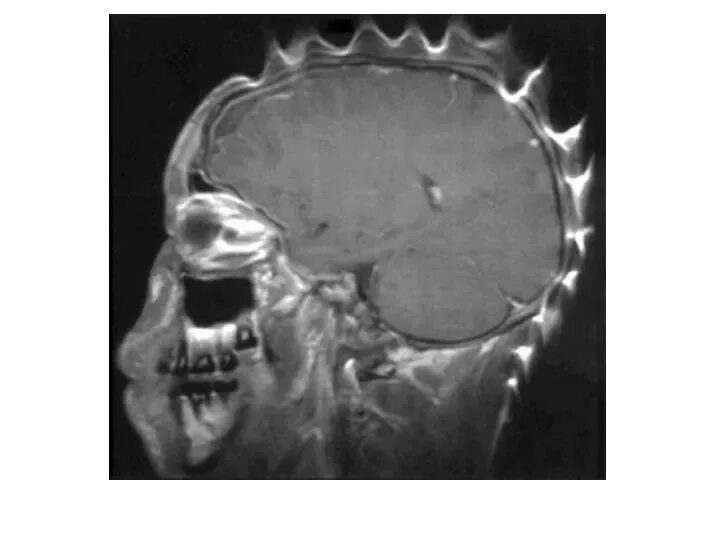

Мрт если есть металлические зубы